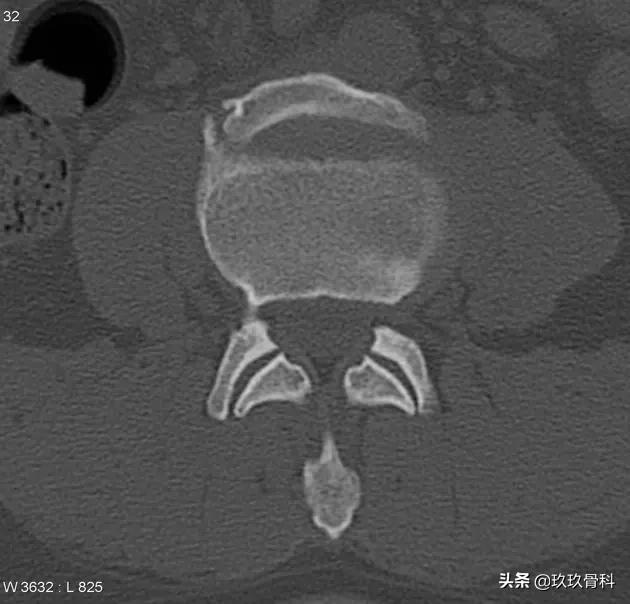

患者伴有长时间的腰背部疼痛史。L4椎体前上缘局灶性骨质缺损,区域内可见一游离的骨性信号。

MRI显示 游离的骨块呈长T1短T2信号,游离骨块与椎体间缺损区与同层椎间盘等信号。